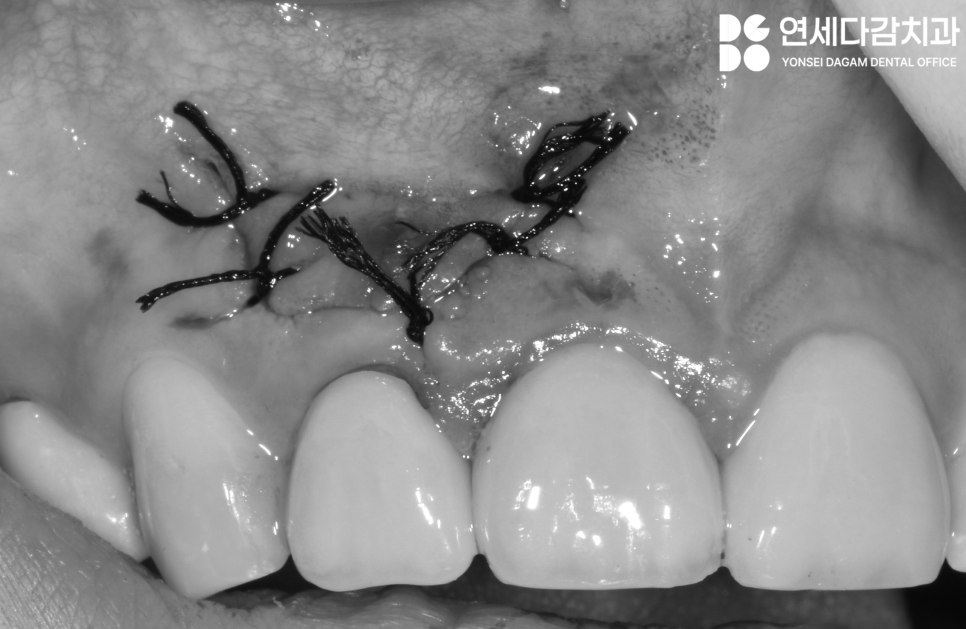

이때 골소실이 심했던 경우

가락동 치과 에서는

뼈이식을 병행하기도 합니다.

마무리 단계로 연조직 피판을

제자리에 위치시키고

봉합하여 마무리합니다.

술 후 부종과 통증이 있을 수 있으며

며칠 내에 점차 감소하게 되고,

봉합사는 보통 1주일 후에

풀게 됩니다.

후에는 치은에 흉터가 남을 수 있으나

점차 더 아물면

말끔하게 치유될 수 있습니다.